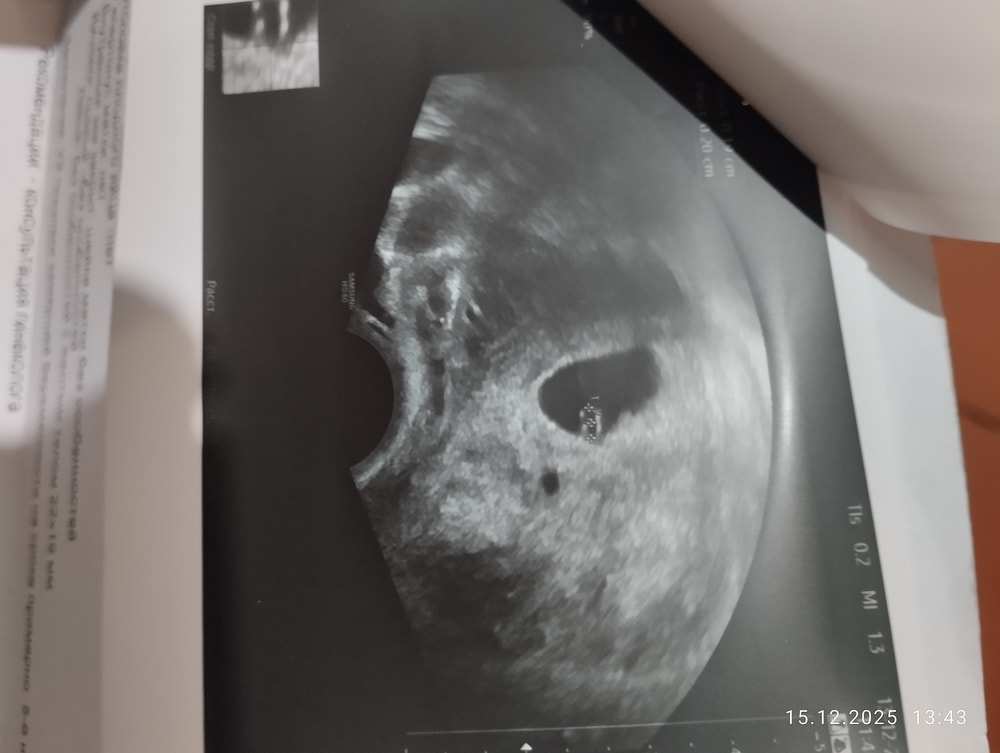

На фото заключение от 13 декабря (4 узи) : желточный мешок и знаки вопросов далее, что это может значить? На снимке видны были две полосочки, ктр не увидели, сомнение берёт.

Почему-то к верх ногами фото.) извините. Но почему стало два жм?

4 УЗИ 13.12(через 2 дня): свд 18 мм, ктр 4 мм или 2

Наиболее адекватно выглядит только последнее УЗИ, на нем нормально померили плодное яйцо (при этом получается, что первые три можно вообще не смотреть, иначе у вас плодное яйцо вымахало за 3 дня (между 2 и 4 УЗИ) на 10 мм, это невозможно, да и на фотографии видно, что оно не в 2 раза больше чем желточный мешок, а больше).

Если смотреть только последнее, то там размеры плодного яйца не соответствуют сроку, оно маловато. Если там желточный мешок 4 мм, то он нормального размера, если 2 мм желточный мешок и 2 мм эмбрион, то желточный мешок маленький и эмбрион тоже.

Евгения, просто после этих четырёх узи все спутано, срок 8 недель , а сердцебиение не наблюдается, и почему-то на крайнем узи на снимке стало две полоски, как будто два желточных мешка. Может позднее разделение началось на двойню? Сейчас ставят замершую беременность под вопрос, мол, сердца не слышно. И куда делся ктр?